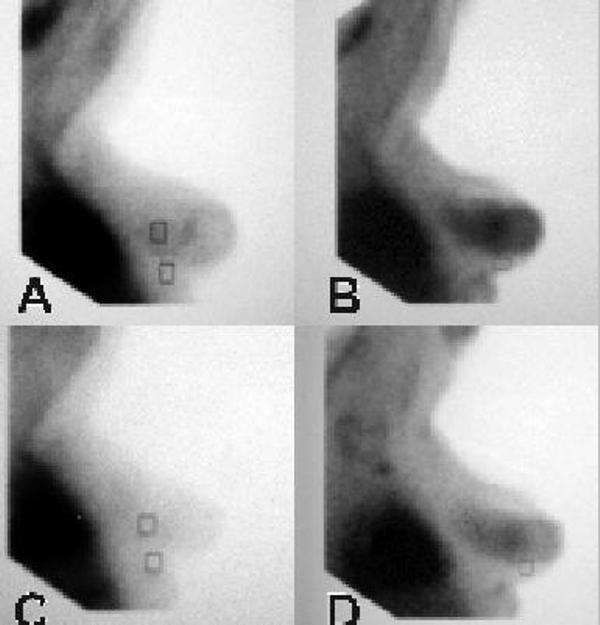

We present a case of severe epithelial hyperplasia in a 47-year-old woman with increased breast density submitted to scintimammography by the proliferation-imaging tracer Technetium-99m-labelled pentavalent dimercaptosuccinic acid, before and after an oral ibuprofen treatment for 4 weeks. The radiotracer uptake after ibuprofen intake was significantly reduced, both visually and by semi-quantitative analysis, based on a calculation of lesion-to-background ratios.

In proliferating breast lesions, scintigraphically displayed reduction in Technetium-99m-labelled pentavalent dimercaptosuccinic acid uptake may indicate inhibition by ibuprofen in the pathway of malignant epithelial cell transformation.

我们报告一例47岁女性严重上皮增生病例,该女性乳腺密度增加,在口服布洛芬治疗4周前后,通过增殖显像剂锝 - 99m标记的五价二巯基琥珀酸进行乳腺闪烁显像。基于病变与背景比值的计算,布洛芬摄入后,放射性示踪剂摄取在视觉上和半定量分析中均显著降低。

在增殖性乳腺病变中,闪烁显像显示锝 - 99m标记的五价二巯基琥珀酸摄取减少,可能表明布洛芬对恶性上皮细胞转化途径有抑制作用。